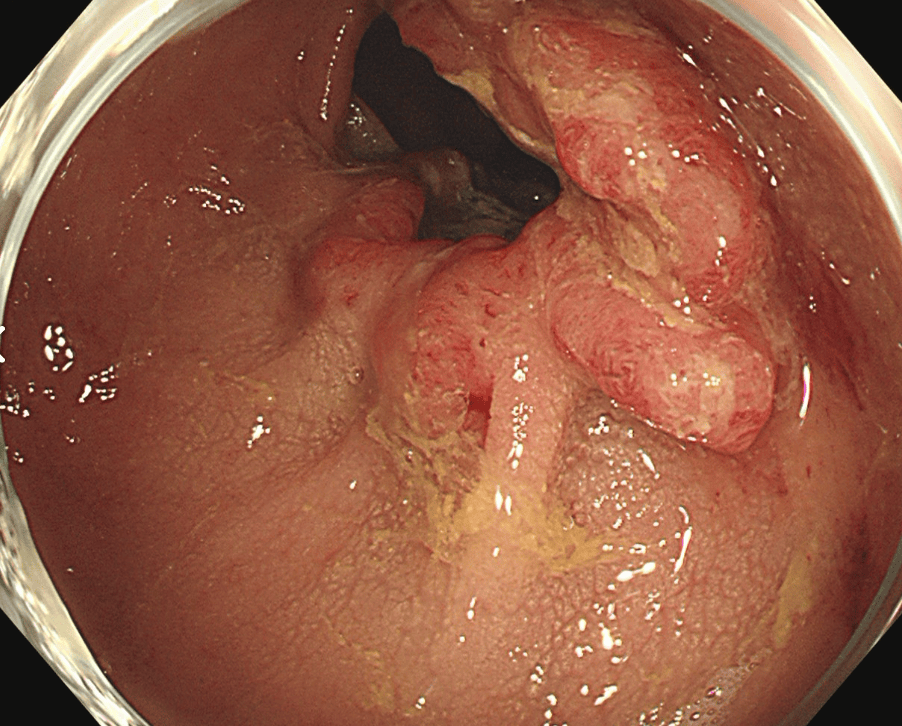

閉塞性大腸がんに対する大腸ステント治療

大腸がんが進行し腸が詰まってしまう閉塞性大腸がん(大腸がん腸閉塞)に対する治療です。従来は人工肛門を造設して対処していましたが、人工肛門はケアの負担やにおいに対する不安などからQOL(生活の質)低下が避けられません。そのため当院ではステントと言われるメッシュ構造の金属製の網を用いて詰まりを解消し、人工肛門を回避する治療を行っています。大腸ステント治療は緩和治療を目的に行う場合と根治手術前に全身状態の回復を目的として行う場合があります。

治療前

ステント留置後(内視鏡画像)